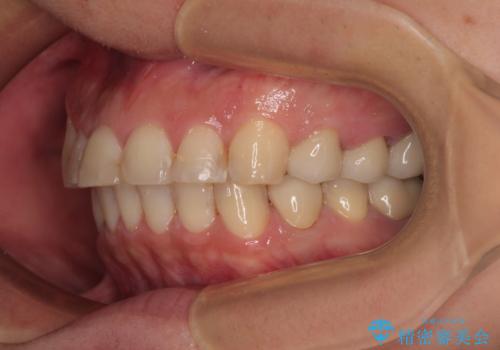

矯正治療にやや時間がかかりましたが、歯列はきれいに整い、気になっていたむし歯や銀歯は自然な色合いに仕上がりました。